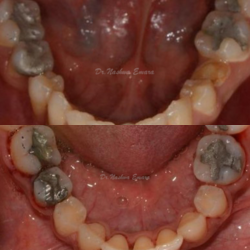

Children

Full Mouth White Fillings